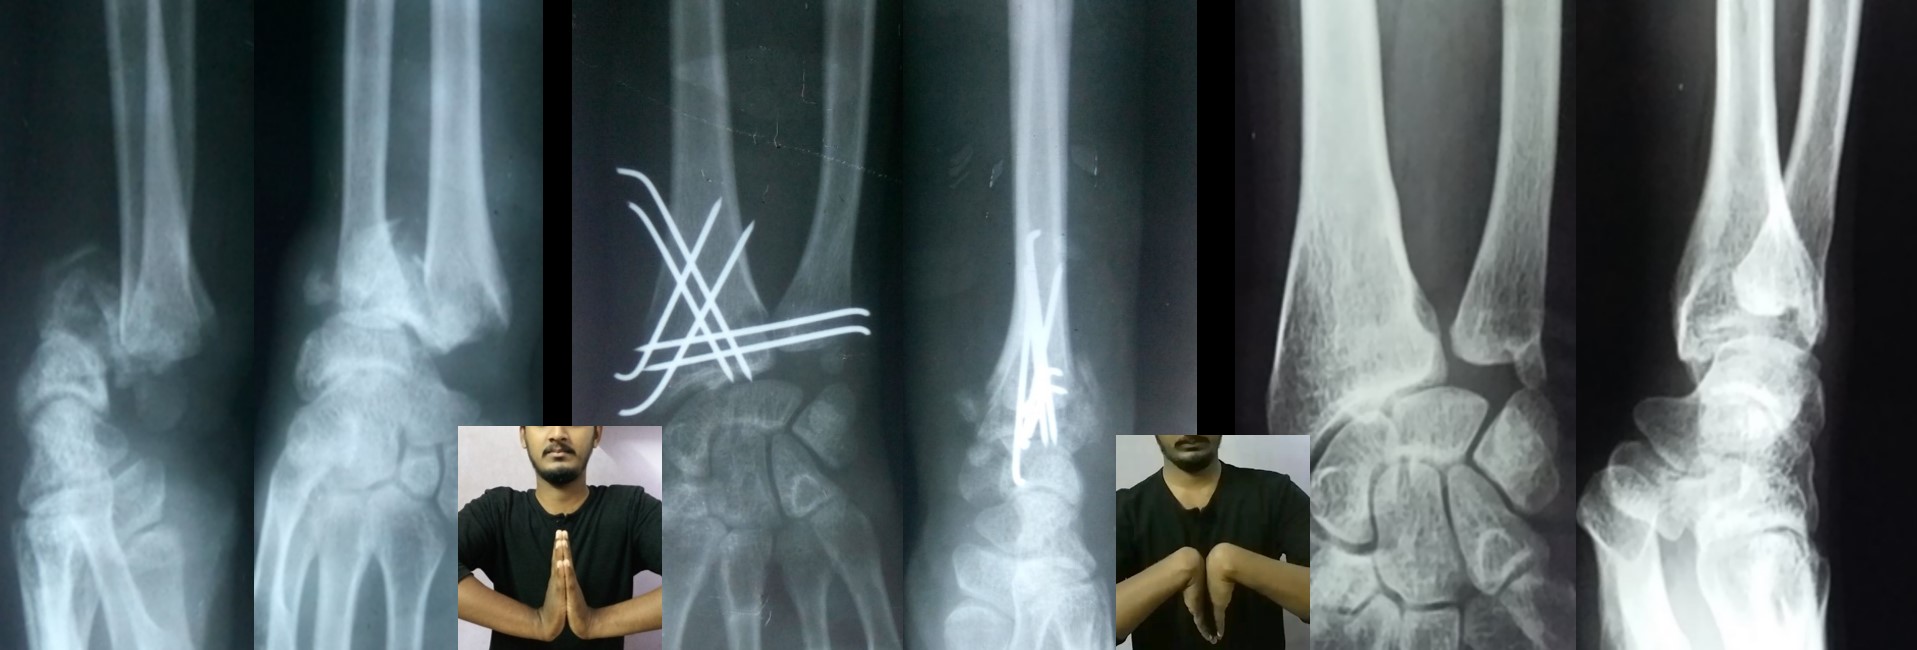

CRPP ( Closed Reduction Percutaneous Pinning )

The CRPP technique for intra-articular fracture distal radius was published in their journal of AAOS-Global Research & Reviews- (June 2020-volume-4-issue 6

• No skin incision is required, and fracture heals faster than open surgeries as there is no iatrogenic soft tissue damage or disturbance to the fracture hematoma.

• No implants projecting outside the skin and hence painless adjacent joint movement is possible immediately after CRPP.

• Early return to some of the personal works like writing, dressing, washing etc from the 2nd postoperative day onwards after CRPP of the fracture distal radius.

• Due to the early implant removal, the functional capacity returns to normal within a short period.

·        A Novel Method of Closed Reduction and Percutaneous Pinning with Six K-wires for Intra-articular Fractures of the Distal Radius. Anilkumar Vidyadharan, MBBS, D. Ortho, JAAOS Global Research & Reviews (June 2020-volume-4-issue 6)